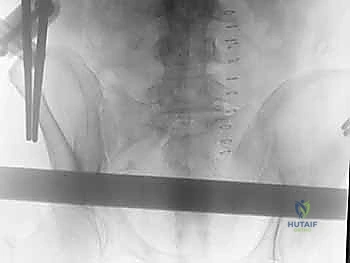

الخطوة الرابعة: تركيب الإطار الخارجي (The Frame)

بمجرد تثبيت المسامير بقوة في العظام، يتم توصيل الأجزاء الخارجية منها بأعمدة (قضبان) مصنوعة من ألياف الكربون (Carbon fiber) أو المعادن الخفيفة باستخدام مشابك قابلة للتعديل.

الخطوة الخامسة: الرد (Reduction) والتثبيت النهائي

يقوم الدكتور هطيف يدوياً بالضغط على الحوض لإغلاق "الكتاب المفتوح" (رد الكسر إلى وضعه الطبيعي التشريحي). بمجرد تحقيق الوضع الأمثل والتأكد منه عبر جهاز الأشعة، يتم إحكام ربط المشابك لتثبيت الإطار الخارجي بشكل صلب ونهائي، مما يمنع أي حركة إضافية للحوض ويوقف النزيف فوراً.